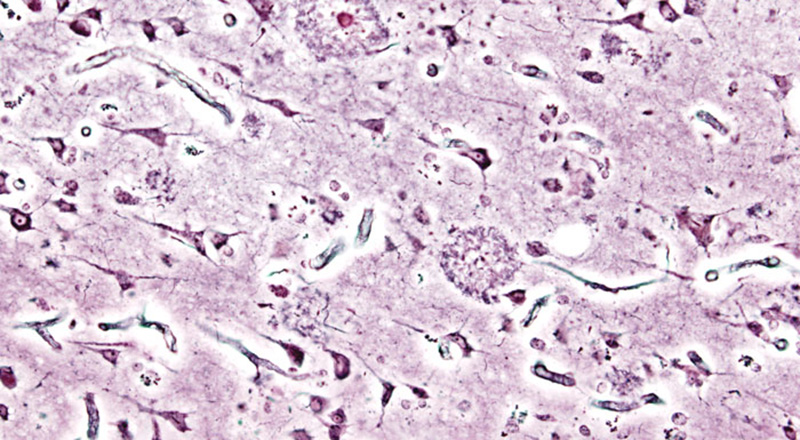

Le aziende farmaceutiche Biogen (Stati Uniti) ed Eisai (Giappone) hanno annunciato di avere annullato nuovi test clinici sull’aducanumab, un farmaco che finora era stato considerato promettente per trattare il morbo di Alzheimer, la forma più comune di demenza degenerativa. La sospensione dei trial clinici è un altro fallimento in uno degli approcci più sperimentati negli ultimi anni per contrastare l’Alzheimer: intervenire sulla betamiloide, la proteina che causa l’accumulo di placche nei neuroni rendendoli sempre meno reattivi e funzionali. I previsti trial clinici sono stati ritenuti “inutili” da un gruppo di ricerca indipendente nominato dalle due aziende farmaceutiche, che in questi anni avevano collaborato allo sviluppo del nuovo farmaco.

I ricercatori sanno da tempo che la betamiloide riveste un ruolo nello sviluppo del morbo di Alzheimer, malattia comunque complessa e dai fattori scatenanti piuttosto sfuggenti. Sono stati quindi sperimentati diversi approcci per inibire o tenere sotto controllo questa proteina, per evitare che causi danni nei neuroni. Gli approcci seguiti finora non hanno però portato a progressi significativi, soprattutto nei test clinici e nelle sperimentazioni sui pazienti. Alcune delle più grandi aziende farmaceutiche, come Merck & Co., hanno avuto problemi analoghi e sono state costrette a rivedere i loro progetti sull’Alzheimer dopo milioni di euro di investimenti.